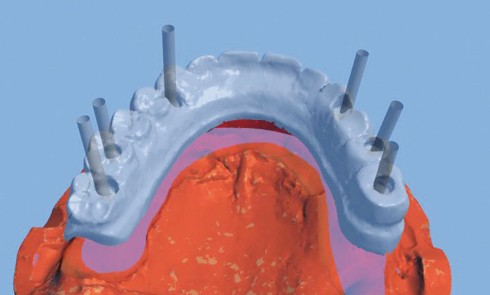

Nous vous proposons dans cet article de détailler pas à pas la réalisation au laboratoire d’une prothèse complète maxillaire implanto-portée,...Les implants courts au maxillaire postérieur : une alternative fiable et peu invasive

Les implants courts (≤ 8 mm) peuvent constituer une bonne alternative aux implants standards. Le recours aux techniques d’augmentation osseuse peut...La mandibule atrophiéeRestauration prothétique avec des attachements Locator® angulés